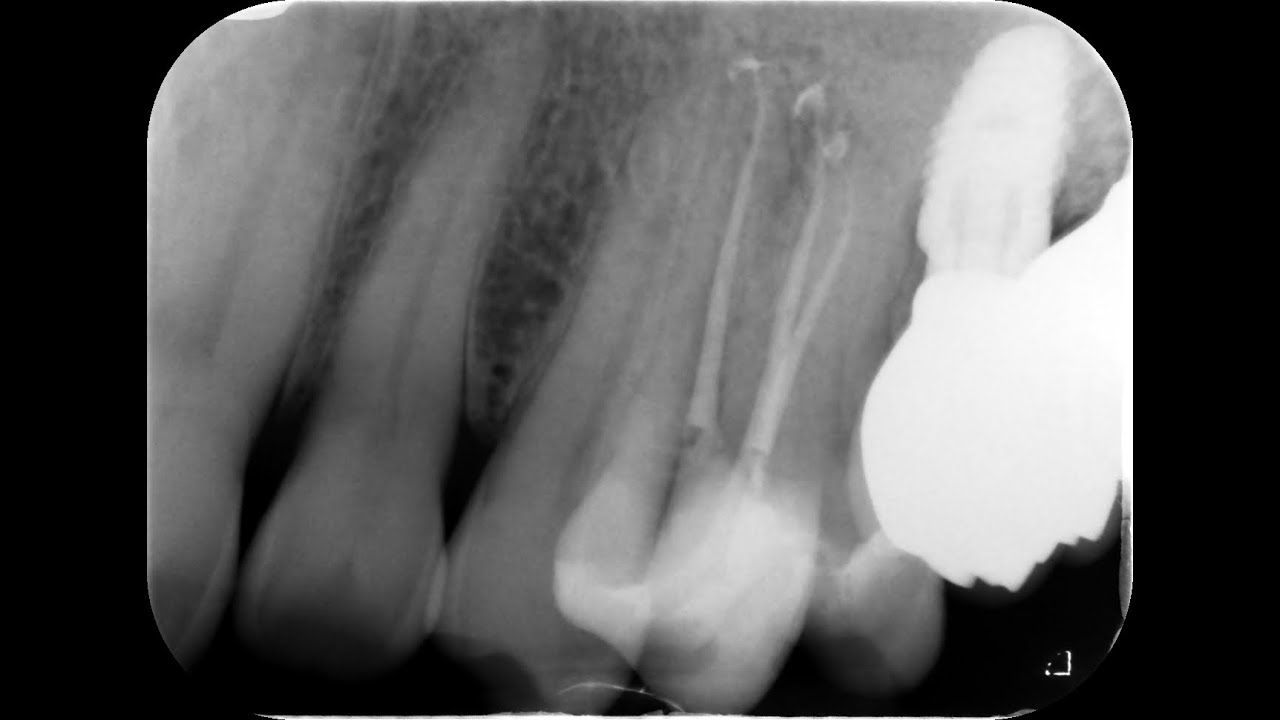

algumas referências bem importantes com relação ao bloqueio do nervo ovol superior posterior e algumas coisas que a gente tem que est atento é que na infiltração e no bloqueio desse nervo nós precisamos fazer uma infiltração para trás para dentro e para cima e o ponto de infiltração ele é no fundo de suco acima na região ali do segundo molar superior e como é que a gente faz a angulação correta primeiro eu vou pensar no plano oclusal da maxila e eu tenho que angular em 45º em relação a esse plano oclusal aqui eu já tô direcionando

minha agulha para cima Eu também preciso angular 45º em relação a um plano cusal para dentro porque a maxila é côncava se eu vou nesse sentido aqui eu vou muito lateralizado então eu angulo para dentro e uma outra referência que se pode usar em relação ao plano ocul usal dos molares é também jogar 40 G para trás Então nesse sentido aqui eu estou indo Obrigatoriamente para cima para trás e para dentro ou para Medial então eu vou fazer o meu ponto de infiltração aqui acima na junção na no fundo de suco na região do segundo

molar e vou aplicar vou fazer infiltração para cima para trás e para dentro e aqui seria meu ponto de aplicação para atingir o nervo Lar superior posterior antes dele entrar na maxila antes dele entrar nas foraminas da maxila e o adendo que eu preciso fazer em relação ao bloqueio do nervo maxilar é que a gente vai usar esse mesmo princípio que eu falei aqui só que a gente vai fazer com uma agulha longa e vai introduzir cerca de 30 mm que é para chegar lá na fossa périgo palatina próximo de onde o nervo maxilar emerge